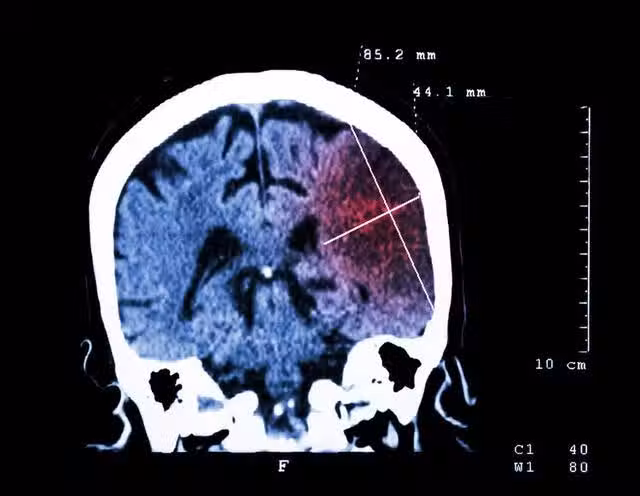

50歲女子,飯後腦梗癱瘓,警告:中老年人晚飯後,儘量少做5件事

如今腦梗的發病率越來越高,年輕人也在不斷的被腦梗盯上,誘發腦梗的因素很多,大多數與不良的生活習慣有關。日常要特別注意,特別是飯後這5個壞習慣要改正,以免被腦梗盯上。